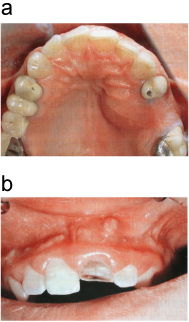

口蓋膿瘍、歯槽膿瘍

a:左側口蓋部に膿瘍形成を認める。

b:上顎左側中切歯根尖相当部に膿瘍形成を認める。